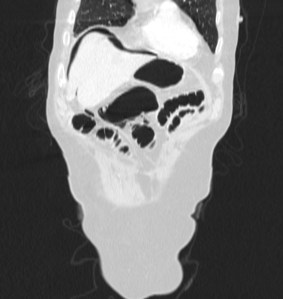

Paciente con diarrea y vómitos y dolor abdominal intenso. Antecedentes de fibrilación auricular. Analítica con discreta leucocitosis.

Se sospecha Isquemia intestinal. Veamos las pruebas complementarias de imagen:

En conclusión, estamos ante un cuadro de posible isquemia intestinal perforada, de ahí el neumoperitoneo.